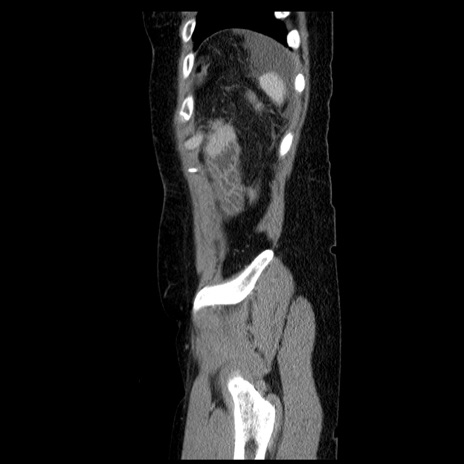

症例6(矢状断像)

【症例】50歳代女性

【主訴】下腹部痛

【現病歴】本日朝より下痢2回あり。 昼食を食べた後、嘔吐3回、下腹部痛認め、症状軽快せず、当院救急搬送。

最終食事:本日昼(生ものなし)。 昨日の夜、刺身を食ぺたとのこと。周囲に同様の症状の者なし。普段、排便は毎日あるとのこと。

【既往歴】卵巣癌術後(8年前に当院で卵巣摘出)

【身体所見】 意識清明、腹部:平坦、腸蠕動音→、やや硬、下腹部自発痛・圧痛あり、反跳痛あり、筋性防御なし。

【データ】WBC 16000、CRP 0.01